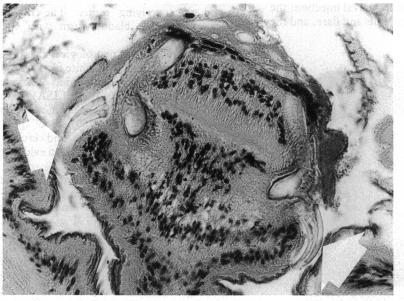

A case of subretinal cysticercosis was treated with laser coagulations round the cyst prior to surgery. In-toto removal of the living cysticercus was performed by pars plana vitrectomy. Two weeks after surgery 25/20 vision was regained. Histopathology of the cyst confirmed the clinical diagnosis.

https://cdn.ncbi.nlm.nih.gov/pmc/blobs/6859/1042475/a8e6b1751050/brjopthal00571-0050-a.jpg